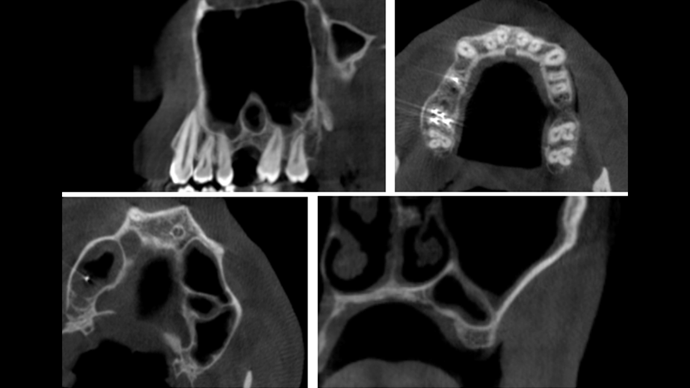

Clinical case: Installation of dental implants in complicated anatomic conditions using crest lifting methods

- Courtesy of Dr.Alexander Lysov, Russia -

AnyRidge, complicated anatomic conditions, crest lift, MICA Kit, Dr. Alexander Lysov, bone regeneration, GBR, #26, maxillary posterior

AnyRidge implant system, MICA Kit